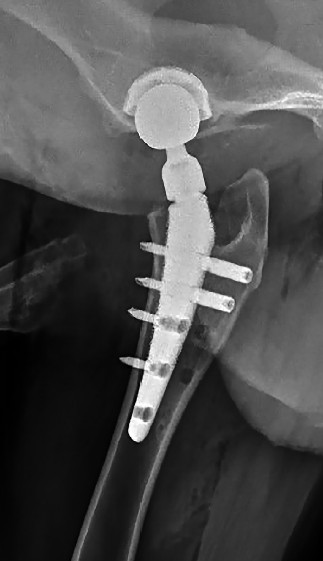

Разработан алгоритм фиксации бедренного компонента, обеспечивающий его первичную остеоинтеграцию, заключающийся в строгой последовательности проведения бикортикальных и монокортикальных винтов. Энергодисперсионная рентгеновская спектроскопия подтвердила высокую степень интеграции костной ткани в ячеистых зонах импланта, которые занимают основную часть эндопротеза. Это свидетельствует о надежном связывании ножки протеза с костным ложем уже на 45‑е сутки после установки, что является ключевым фактором долгосрочной стабильности импланта (рис. 9). Использование двух бикортикальных винтов и модификация последовательности их установки помогли минимизировать нестабильность ножки в послеоперационном периоде. Уменьшение количества винтов позволило снизить общую стоимость операции и сократить объем хирургического доступа, необходимого для их установки (рис. 8).

Рис. 8. Послеоперационная контрольная рентгенография после протезирования тазобедренного сустава с использованием двух монокортикальных и двух бикортикальных винтов. Дистальное отверстие не используется

Источник: составлено А.М. Пантюлиным, И.Ф. Вилковыским.

Fig. 8. Postoperative control radiograph after hip replacement using two monocortical and two bicortical screws. The distal hole is not used.

Source: compiled by A.M. Pantyulin, I.F. Vilkoviskiy.